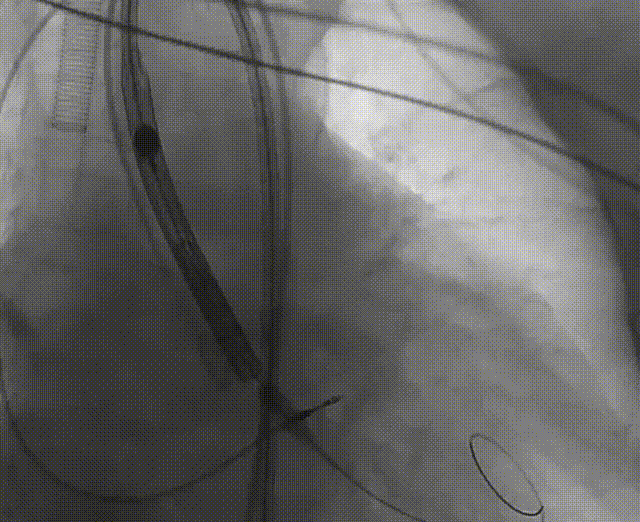

手术流程概括

22球囊扩张,无明显腰增,无造影剂泄露。

瓣膜初始零位释放,释放后位置尚可,决定完全释放。

瓣膜释放后有瓣周漏显示决定进行球囊后扩。

后扩后形态良好,瓣膜展开充分,轻微瓣周漏。